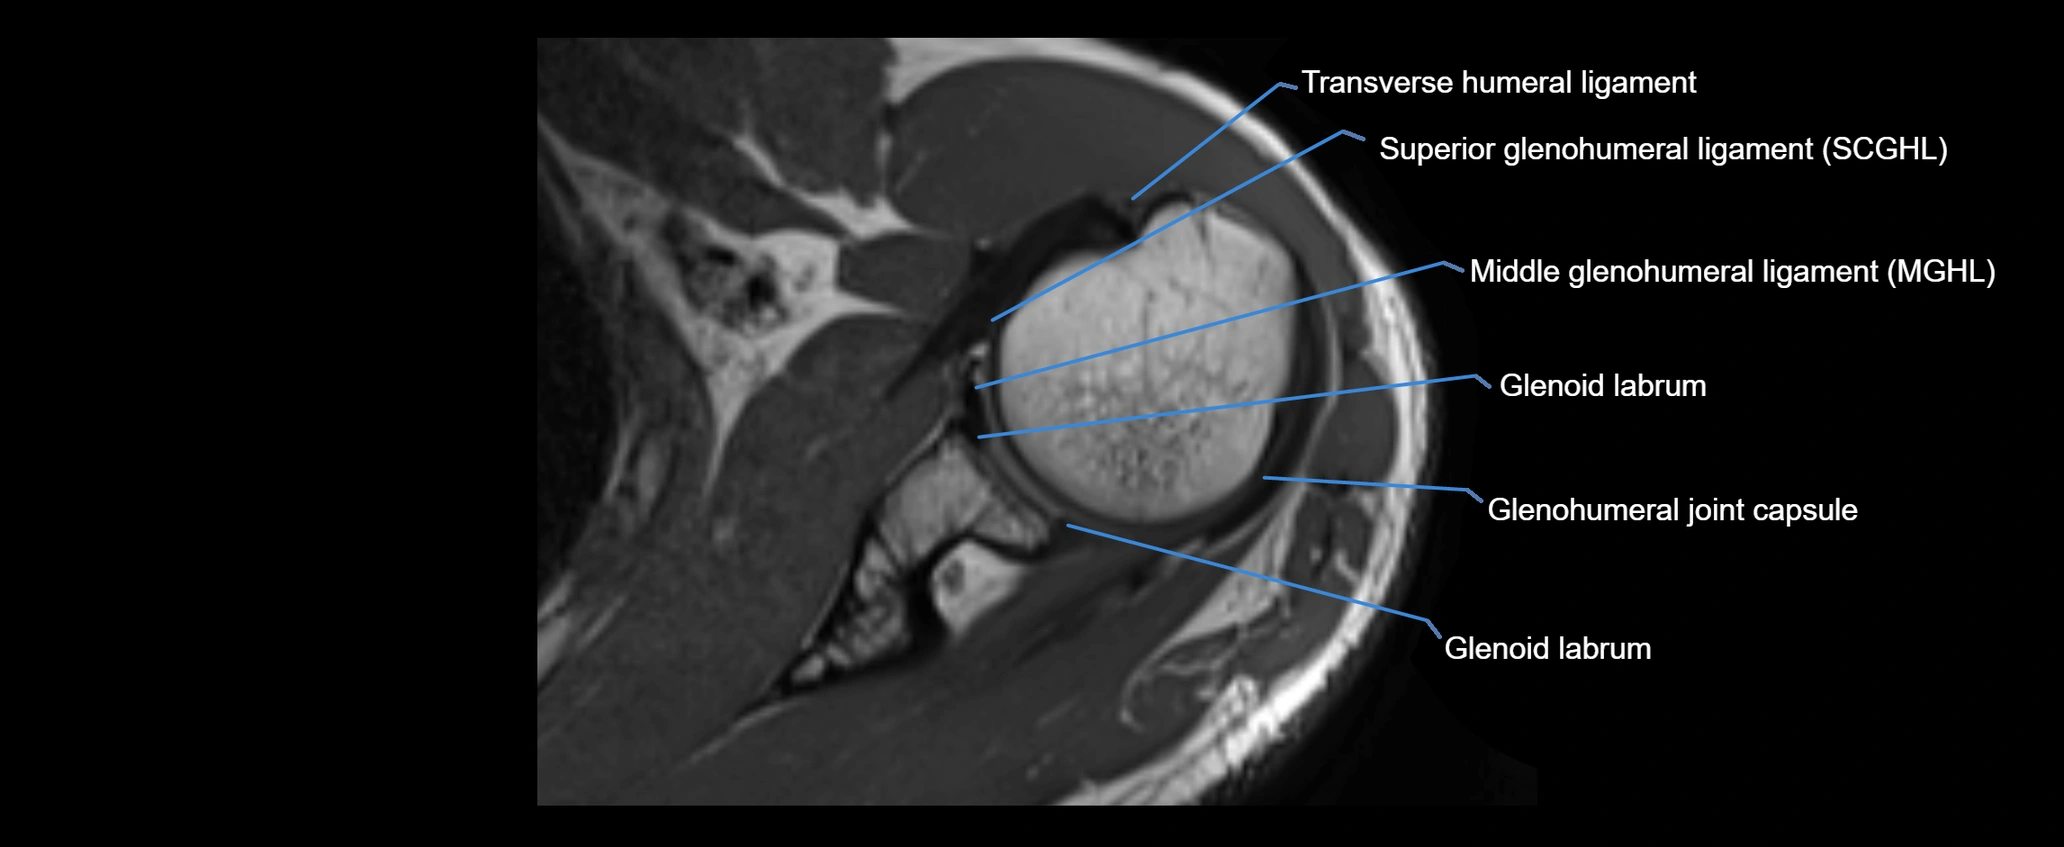

MRI images

image